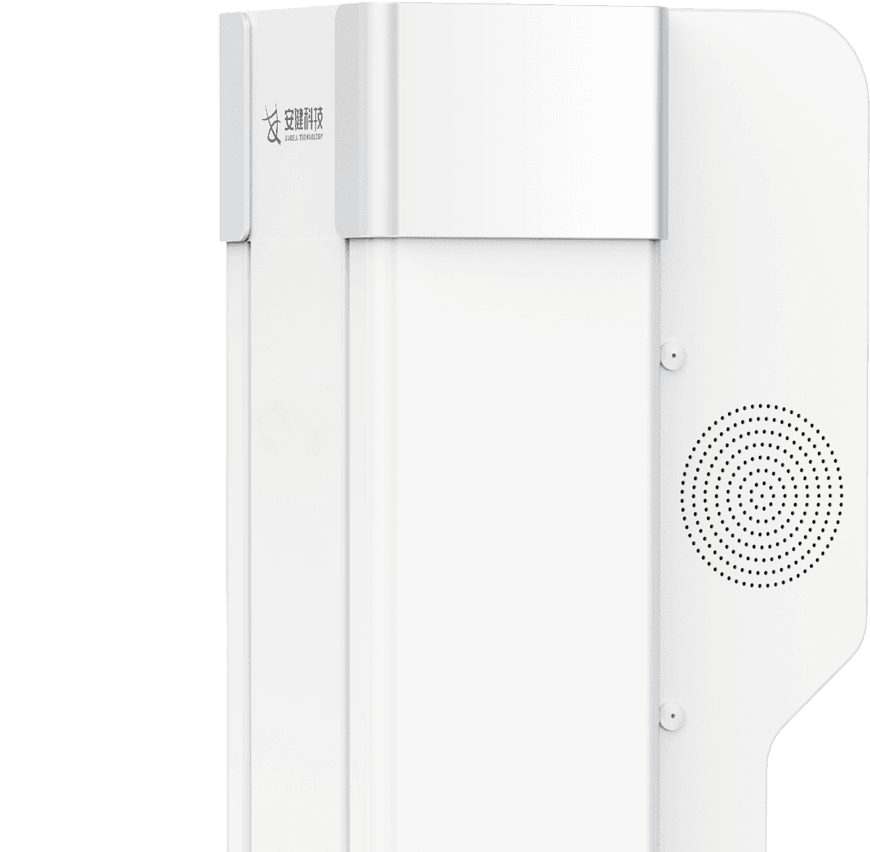

机架内置语音对讲系统

机身内置专业医用对讲系统,语音系统采用高保真音效设计,音质清晰洪亮。

操作医师可隔室进行语音指导摆位摄片,患者在机房内可清晰接受室外操作医师语音指令,提升摆位摄片检查的安全性与效率。